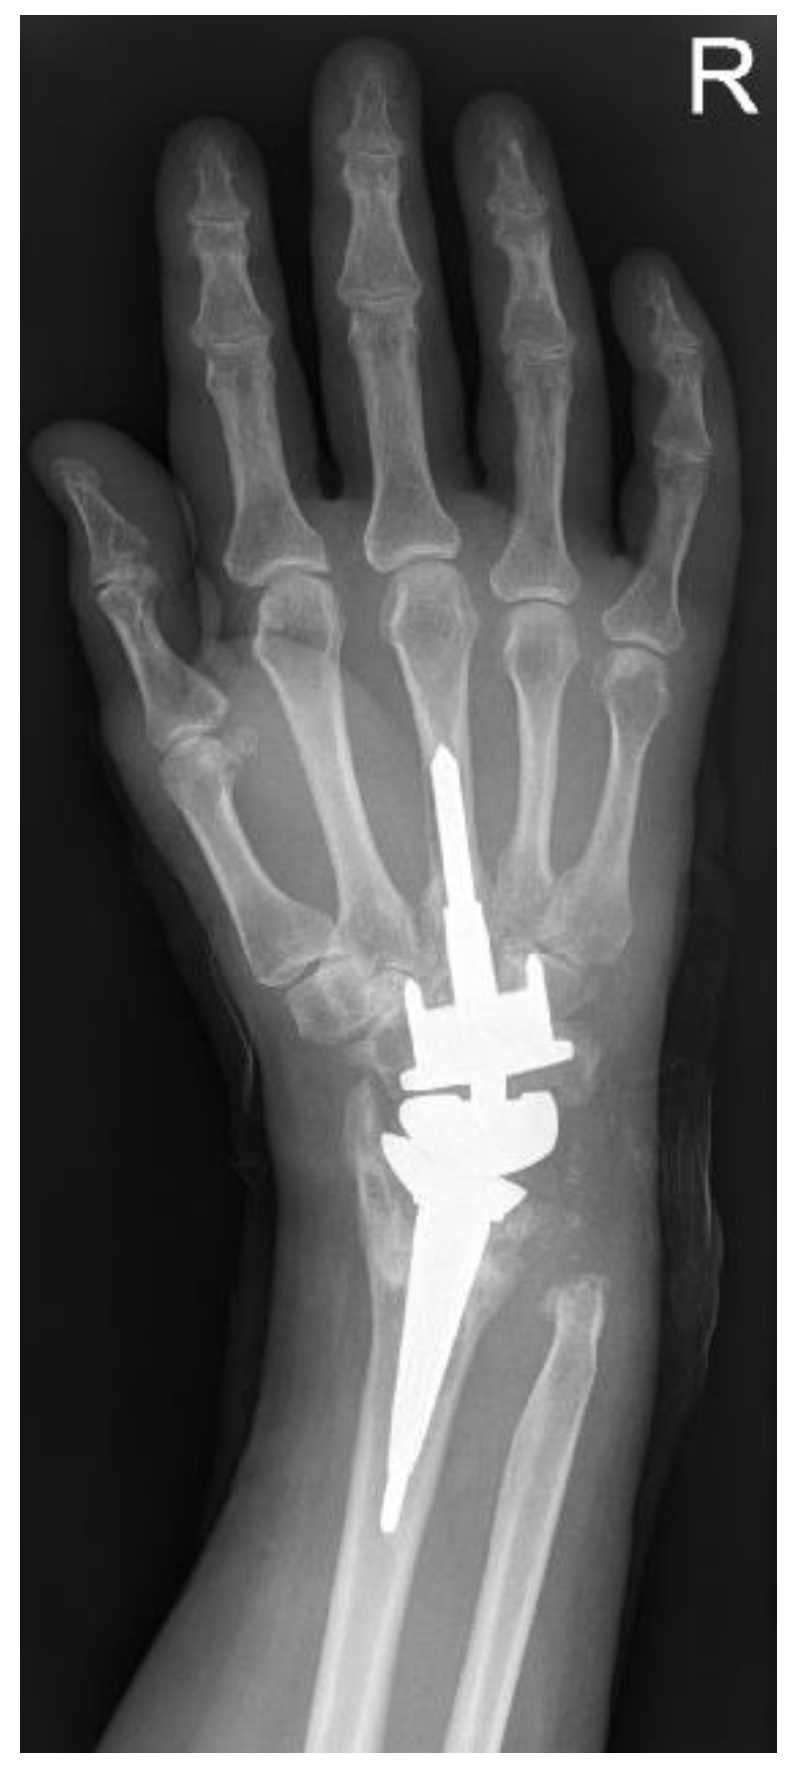

Developed as an alternative to arthrodesis, total wrist arthroplasty (TWA) not only provides pain relief but also preserves wrist movement and function. The carpal anchorage and the correct balancing of the tendons continue to be problematic. These have been the subject of continuous improvement of implants to date. The Modular Physiological Wrist prosthesis (MPW®) is a modularly designed, cementless, implantable Titanobium endoprosthesis (Figure 1). The special feature is the encapsulated sliding pairing of the distal olive, which is intended to imitate the mobility of the intercarpal joint line [5]. For bad bone quality, various components are available, including a coupled implant. Thus, in the case of revision surgery, it is not necessary to change all components.

3.8. Radiology

Radiographs of 22 wrists preoperatively and at follow-up could be compared (22/34; 64.7%) (Figure 4). Preoperative X-rays of 12 wrists were not available at follow-up. The average time between the preoperative X-ray and the last X-ray was nearly 8.5 years. Eight prostheses (23.5%) showed no evidence of loosening or other radiolucency, osteoporosis, or cyst formation with proper implant position and anatomically correct joint position. In the remaining endoprostheses, various radiological findings were found in one prosthesis. In 6 prostheses, radiological dislocation or subluxation was found in the follow-up controls (17.4%). In each case, the position of the prosthesis corresponded to that of the preoperative rheumatoid wrist. In 2 prostheses, radiolucency >1 mm was found, which corresponded to a loosened prosthesis (5.8%). In a further 9 prostheses, periprosthetic radiolucency without clinical symptoms was detected (26.5%). Natively radiologically visible osteoporosis was detected in four prostheses (11.8%). Periprosthetic cysts were detectable in 6 prostheses (17.6%).

The calculation of the carpal height index according to Youm was only calculated for the wrists with an inserted prosthesis without luxation malposition (88.9% with the inserted prosthesis or 47.1% related to the total collective) [9]. With a target value of 0.54 ± 0.03 according to Youm, the average carpal height index was 0.50 (0.27–0.61).

Upon comparing the different types of 4th generation prosthesis, the unique feature of the PE in the MPW® prosthesis stands out. This design improves the guidance of the prosthesis, but at the same time leads to early decentralized contact of the components with increased abrasion and the risk of pathological contact and the resulting dislocation (Figure 1).

Figure 4. MPW®-prosthesis. X-ray at time of follow-up, 10 years after primary operation. The carpal component was changed after loosening (see complications).